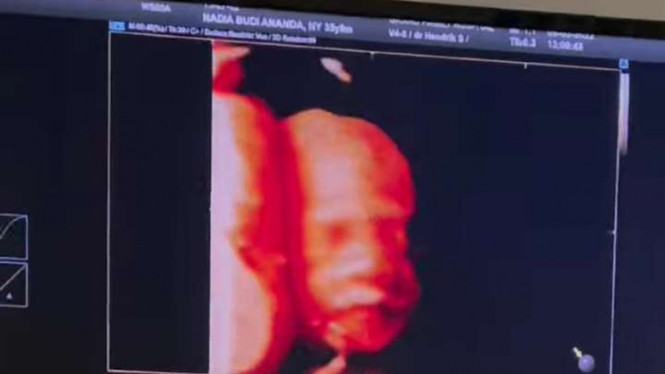

Kini Dea diketahui sudah memasuki usia kandungan 8 bulan. Tak lama lagi dirinya dan sang suami akan bertemu malaikat kecil mereka. Kesakitan wanita cantik tersebut akan segera tergantikan oleh kegemasan bayi kecil yang melengkapi keluarga.

Dea dan suami telah mengumumkan jenis kelamin sang anak. Lewat video pendek yang diunggah di Instagram keduanya menyambut bahagia anak mereka berjenis kelamin perempuan yang akan segera hadir. Keduanya belum membeberkan lengkap nama anak mereka, hanya memberikan julukan baby 'S'.